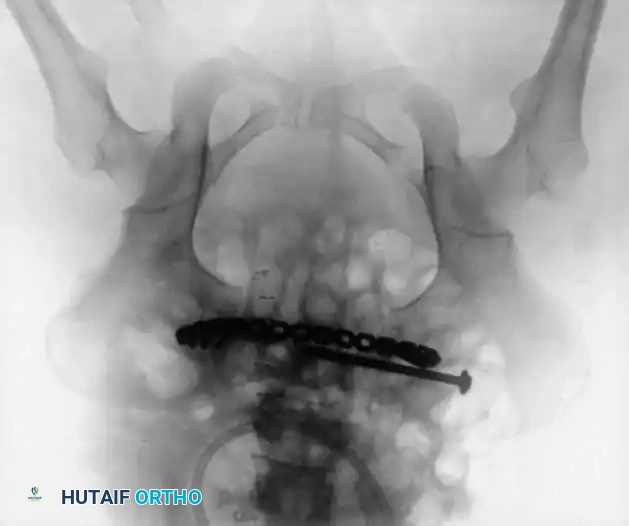

2. Symphyseal Plating (Anterior Ring)

• Positioning: Supine on a radiolucent table.

• Reduction: A Weber clamp or specialized pelvic reduction forceps are placed on the pubic tubercles or via drill holes in the superior rami to reduce the diastasis.

• Fixation: A multi-hole, stout pelvic reconstruction plate (typically 4 to 6 holes) is placed superiorly. Screws must be directed carefully to avoid joint penetration or bladder injury.

4. Posterior Tension Band Plating

For comminuted sacral fractures or when percutaneous corridors are unsafe, open reduction and posterior tension band plating (or lumbopelvic fixation) may be required. This involves placing plates across the posterior ilium to the sacrum, effectively recreating the posterior ligamentous tension band.